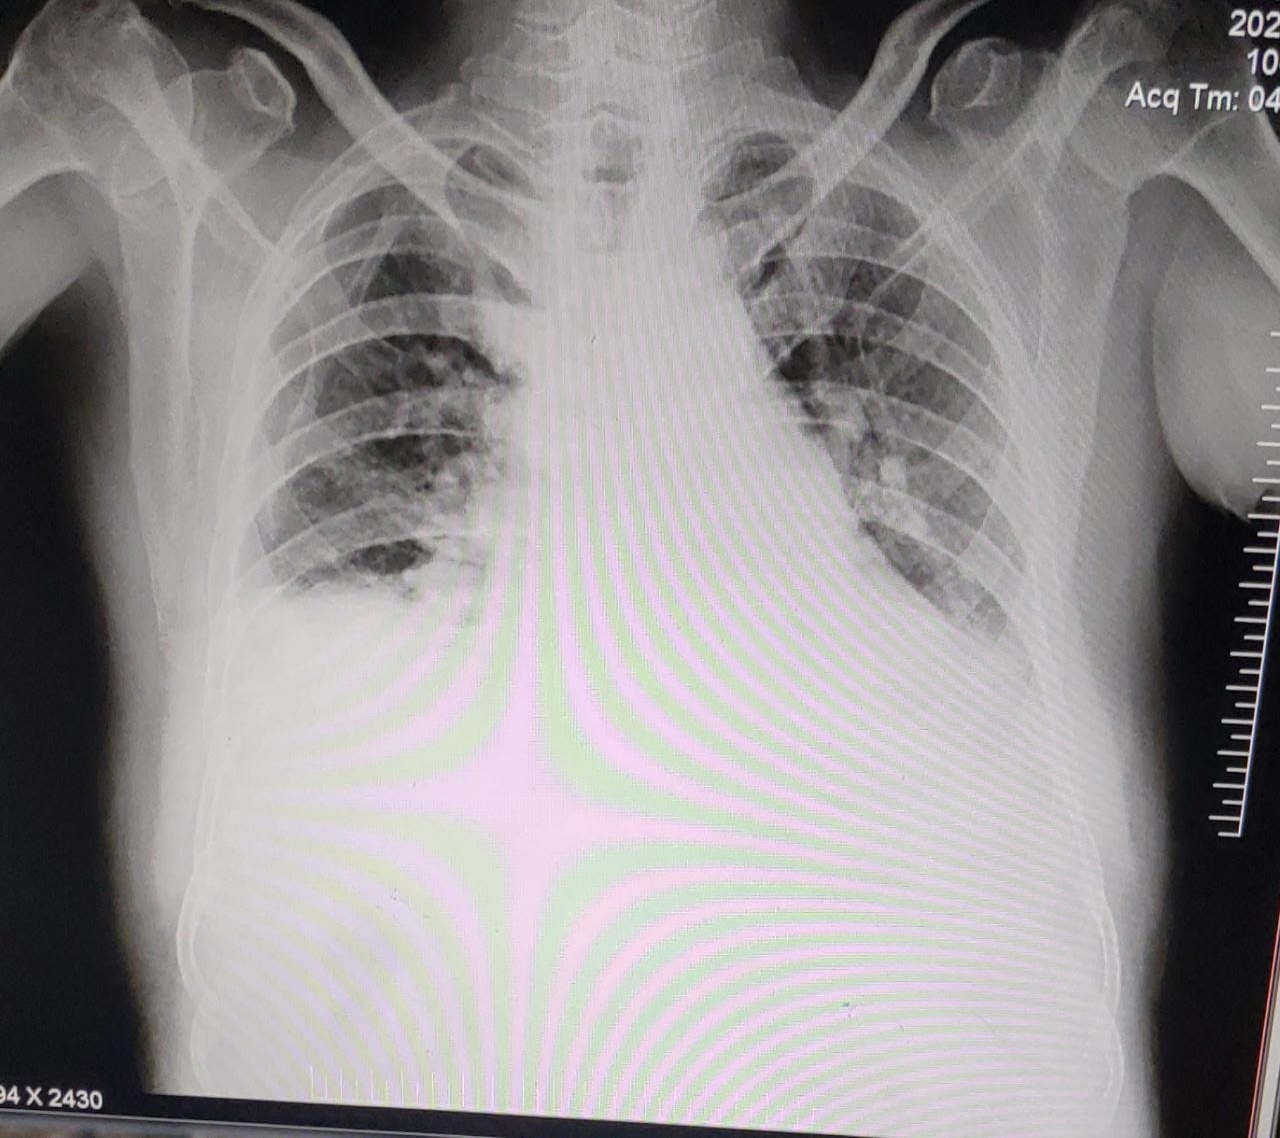

Chest X ray